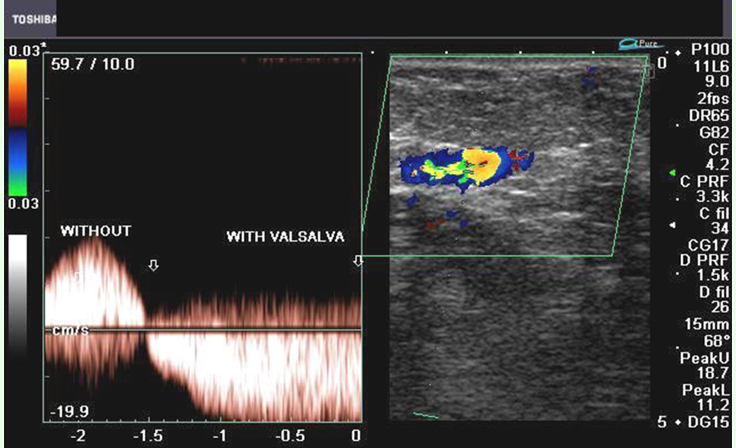

what is the normal response to valsalva maneuver

no flow while bearing down

return of flow upon exhaling

normal or abn

abn

Qs what should you see on spectral doppler during valsalva maneuver when valves are not competent?

reversal of flow